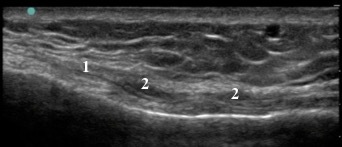

Knee Pes Anserine Transverse Image Medial Collateral Ligament (MCL) over Medial Tibial Neck Oblique Pes Anserine Tendons